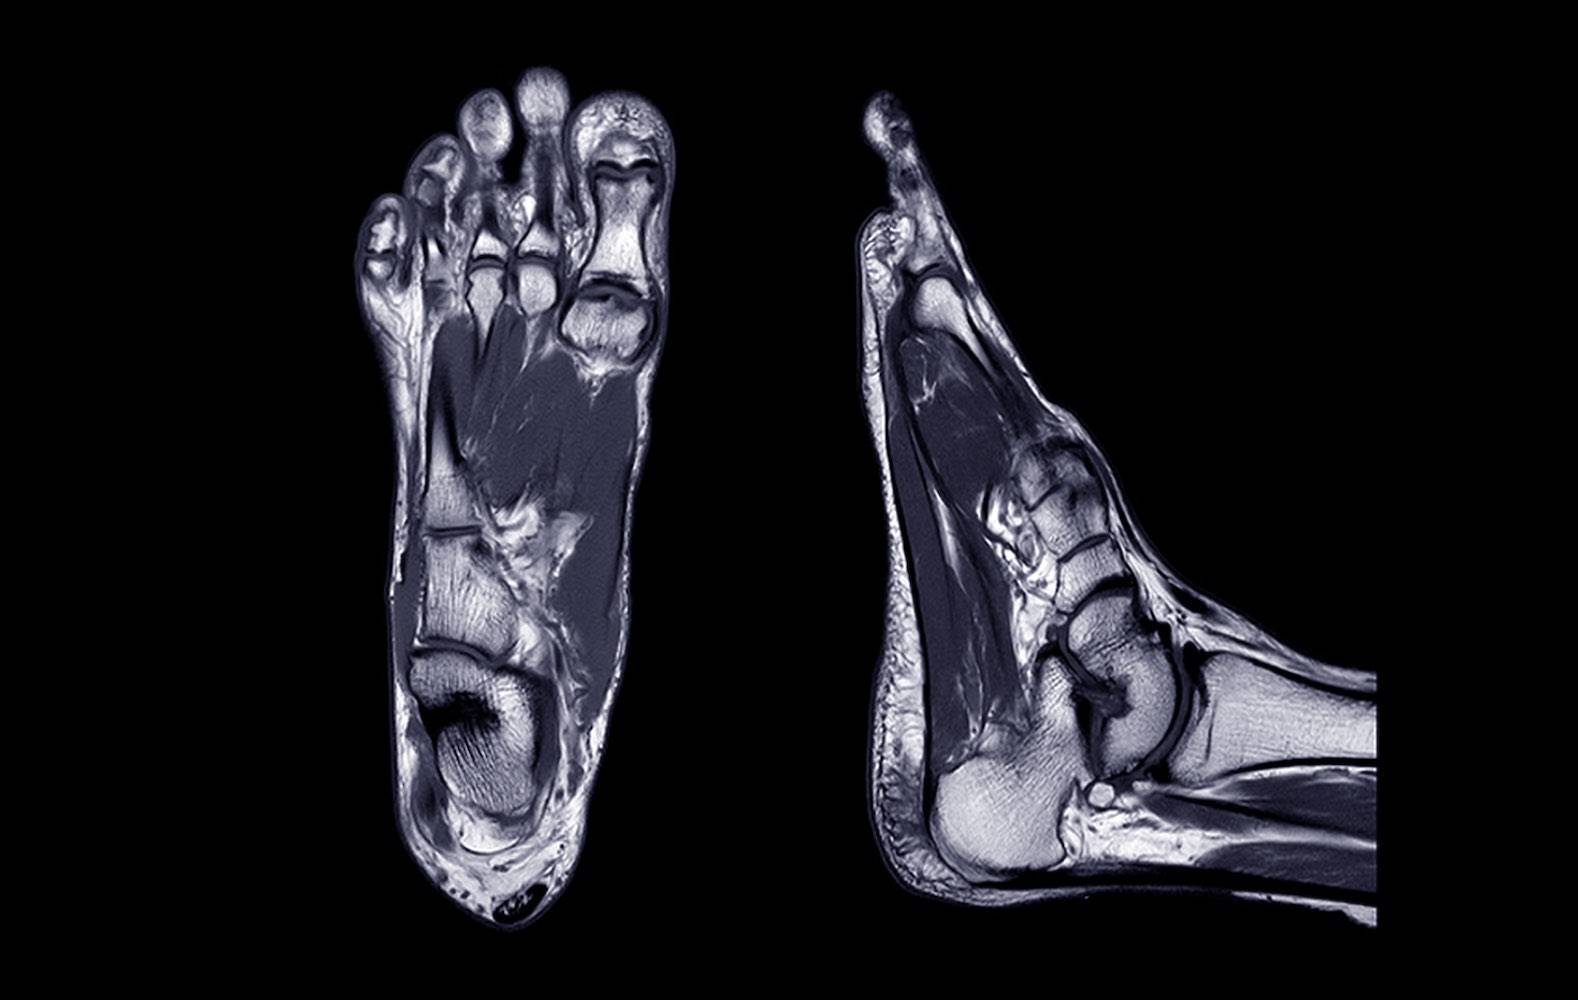

Auf unserer Seite finden Sie umfangreiche Informationen zu orthopädischen Beschwerden und Erkrankungen. Von der Arthrose über Bandscheibenvorfälle bis hin zu Kreuzbandriss und weiteren Sportverletzungen: wir geben Ihnen einen Überblick über die häufigsten orthopädischen Krankheitsbilder, wie sie behandelt werden können und inwieweit ein Bildgebungsverfahren, wie eine (z.B. MRT Knie, Rücken MRT) bei der Diagnose bei der Diagnose unterstützend wirken können.

Viele Betroffene suchen online nach den Ursachen oder Behandlungsmöglichkeiten von Rückenschmerzen, Bänderriss am Fuß oder Bandscheibenvorfall. Einige der orthopädische Beschwerden oder Verletzungen benötigen zu Behandlung eine Bildgebung und Therapie. Alle relevanten Informationen lesen Sie in den jeweiligen Beiträgen.

Unsere Liste zu den häufigsten orthopädischen Problemen ist alphabetisch von A-Z geordnet. So finden Sie schnell und unkompliziert den Beitrag, der Ihnen weiterhilft. Von Krankheiten, über Verletzungen bis hin zu schmerzhaften Zuständen wie Arthrose, Meniskusschaden und Schleimbeutelentzündung – hier finden Sie die wichtigsten Informationen.